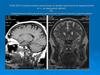

1,5 Тл

Т2

Т1